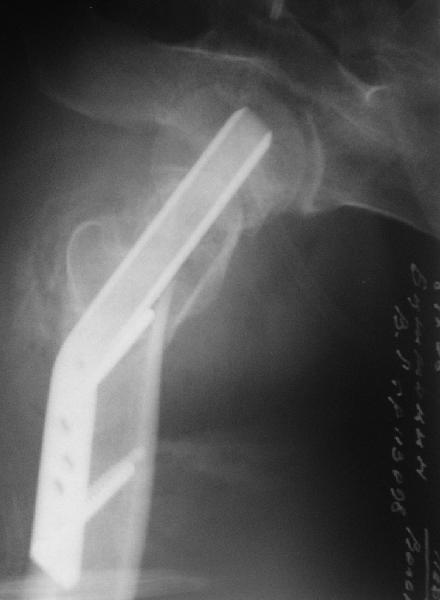

Re: Нелеченный перелом шейки бедра

Приветствую всех. Спасибо за активное участие в обсуждении. Выбрали вариант с остеотомией.

Снимки в приложении.

Надеемся на днях поднять на костыли.